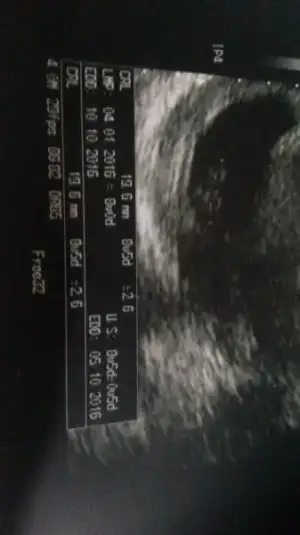

Merhaba kızlar. Bugün kontrol vardı 19.6 mm olmuş bizim yavrucak. USG ye göre 8+5 çıktı ama sat a göre 8. Hangisi doğru bilemedim. Karından baktı bu sefer kalp atışını gördük. Fotosunu yukleyim. Cinsiyetle ilgili yorumlari merak ediyorum :)